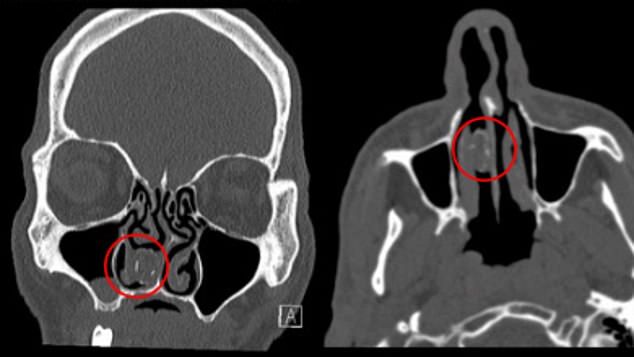

Los médicos le hicieron una placa cerebral porque tenía fuertes dolores de cabeza, un síntoma muy común de los rinolitos. Fue entonces cuando encontraron dicha lesión en su cavidad nasal y lo derivaron con el departamento de otorrinolaringología del Hospital Westmead de Sydney. El paciente reveló que tiene un largo historial de problemas similares: anteriormente tuvo infecciones, sinusitis y obstrucciones en la nariz.

“No supo de la presencia del paquete en su nariz hasta que le hicieron la radiografía”, explicaron los doctores del hospital. “Hasta donde sabemos, este es el primer caso donde se formó un por un depósito de marihuana adquirido en prisión”.